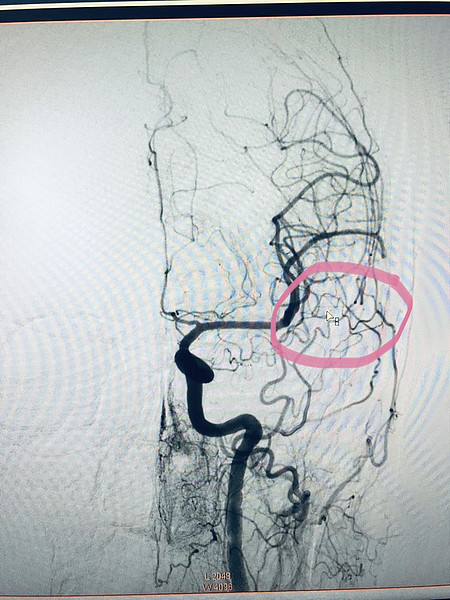

Врачами областной больницы впервые в регионе выполнена операция по удалению редкой сосудистой патологии головного мозга с помощью эндоваскулярных технологий